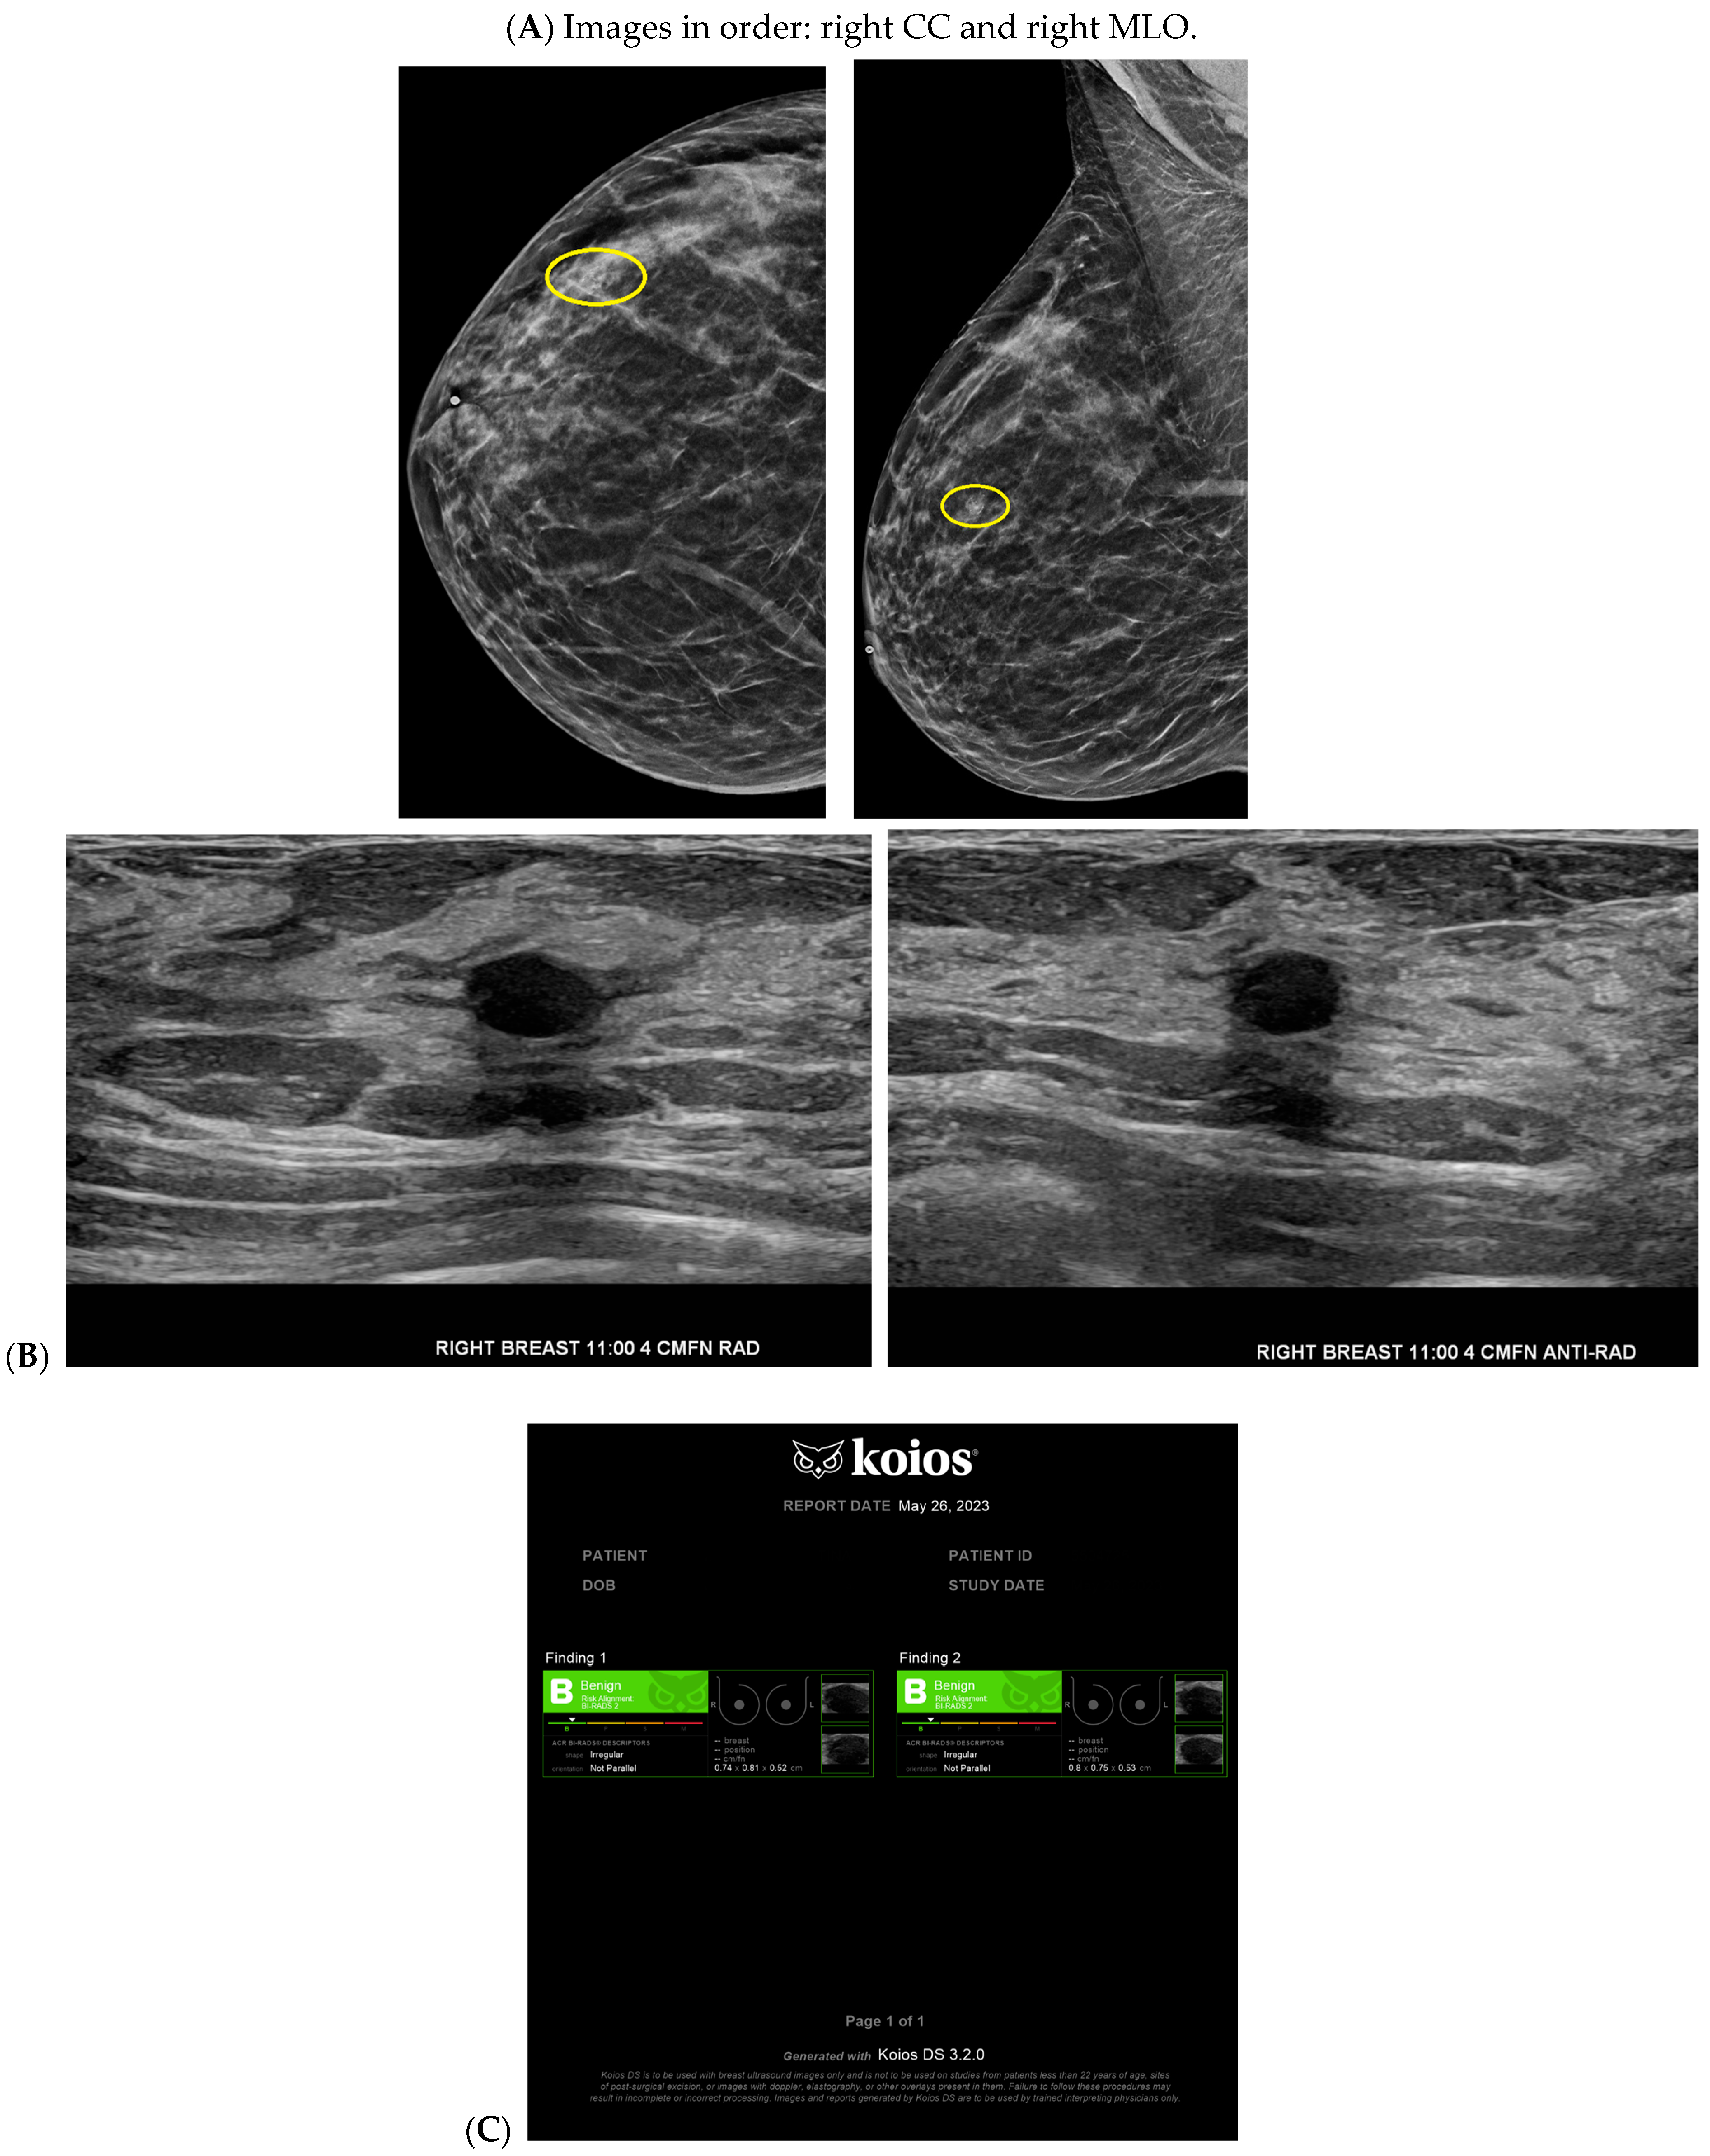

Figure 4.

A benign finding appropriately classified as benign by artificial intelligence (AI): The patient initially presented for a bilateral screening mammogram and a bilateral screening breast ultrasound. A mammogram revealed benign dystrophic calcifications in the upper outer quadrant of the right breast (A). Correlating with findings on the mammogram, ultrasound revealed a complicated cyst showing posterior acoustic shadowing consistent with fat necrosis (B). The AI program Koios recognized this mass as “Benign” (C). Images obtained from the Icahn School of Medicine at Mount Sinai.

Cancer detection systems typically involve neural networks, machine learning, or deep learning developed from training models to recognize patterns, while diagnostic systems use an additional algorithm to classify [17]. Several CNN models have been developed to correlate ultrasound imaging features of a lesion with the four-classification breast cancer molecular subtypes [42]. Our institution uses Koios, which utilizes machine learning and AI to generate the probability of malignancy of a breast finding by evaluating a region of interest (ROI) selected by a radiologist [3,5]. Ultrasound AI has been found to reduce intra- and interobserver variability and to improve accurate BI-RADS classification of sonographic breast findings [3,5]. Ultrasound AI can also increase CDR [5] and reduce the number of unnecessary biopsies [5,43,44] (Figure 1, Figure 3, and Figure 4).